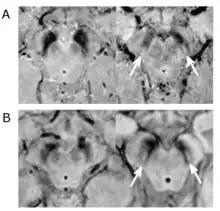

Compared volume of the substantia nigra between a patient with PD and without PD

Substantial loss of melanized dopaminergic neurons in the substantia nigra pars compacta (SNpc) is a major characteristic of PD pathogenesis. Many studies have shown that differential prevalence of PD between ethnic groups is due to differences in the number of melanized neurons in the substantia nigra. Most Indians, compared to populations with European origin, have around 40% lower in number of melanized nigral neurons, however, they also tend not to lose these neurons with age. Although Indians do have a lower SNpc volume, this population tends to have a higher neuronal density as well as number of neurons which is hypothesized to be the reason for a lower incidence rate of PD, but this needs to be expanded upon.[5]